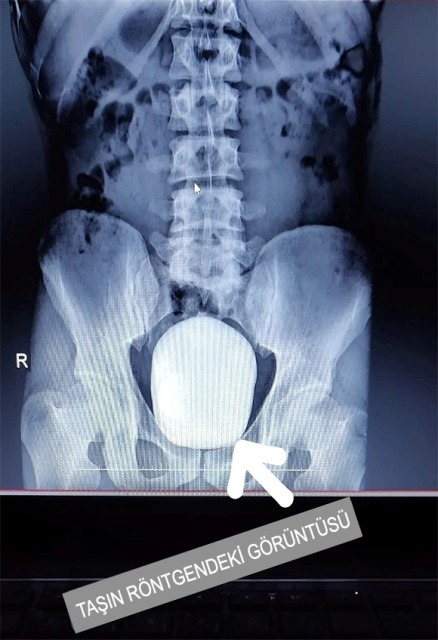

Karaman'da "idrar yaparken yanma" şikayeti ile hastaneye başvuran bir hastanın mesanesinden, bir kilo 50 gram taş çıkartıldı. Karaman'da ikamet eden 27 yaşındaki Barış Yıldız, "idrar yaparken yanma" şikayeti ile Karamanoğlu Mehmetbey Üniversitesi Tıp Fakültesi Karaman Eğitim ve Araştırma Hastanesine başvurdu. Çekilen röntgende hastanın mesanesinde 2 adet büyük çapta taş tespit edildi.Doç. Dr. Güven Erbay ve Dr. Öğretim Üyesi Ahmet Şanlı tarafından yapılan operasyon ile 2 taş alındı.Erbay, yaptığı açıklamada, yapılan tetkiklerle mesanede iki adet taş tespit edilmesi üzerine hastaya acil müdahale ettiklerini belirterek, şöyle konuştu:"Literatürde, tüm dünya genelinde kayıtlara geçen en büyük mesane taşının ağırlığının bin 900 gram olduğu bilinmektedir. Çıkarılan taşların toplam ağırlığı bir kilo 50 gram olarak tespit edildi. Bu büyüklükteki ve ağırlıktaki dev mesane taşının Türkiye sınırları içerisinde çıkarılan en büyük mesane taşı olduğunu düşünmekteyiz."Hastanenin Başhekimi Dr. öğretim üyesi Ahmet Yılmaz ise hastanenin bu tür ameliyatları yapma imkanına ve teknik donanıma sahip olduğunu ifade ederek, "Bundan sonra da bu tür ameliyatları gerçekleştirmeye devam edeceğiz. Bu ameliyatı gerçekleştiren hocalarımıza, emeği geçen herkese teşekkür ediyorum ve tüm hastalarımıza acil şifalar diliyorum." diye konuştu.